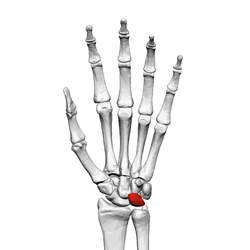

![]() Left hand anterior view (palmar view). Lunate bone shown in red. | |

The lunate bone (semilunar bone) is a carpal bone in the human hand. It is distinguished by its deep concavity and crescentic outline. It is situated in the center of the proximal row carpal bones, which lie between the ulna and radius and the hand. The lunate carpal bone is situated between the lateral scaphoid bone and medial triquetral bone.

The lunate is a crescent-shaped carpal bone found within the hand. The lunate is found within the proximal row of carpal bones. Proximally, it abuts the radius. Laterally, it articulates with the scaphoid, medially with the triquetral, and distally with the capitate. The lunate also articulates on its distal and medial surface with the hamate bone.[1]:708[2]

The proximal surface of the lunate bone is smooth and convex, articulating with the radius. The lateral surface is flat and narrow, with a crescentic facet for articulation with the scaphoid. The medial surface possesses a smooth and quadrilateral facet for articulation with the triquetral. The palmar surface is rough, as is the dorsal surface. The dorsal surface is broad and rounded. The distal surface of the bone is deep and concave.[3]